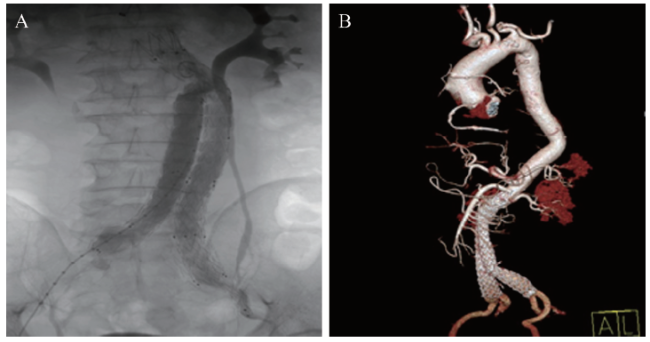

术中取右股动脉及左股动脉相应部位皮肤切口,造影见腹主动脉瘤巨大,直径约10 cm,长约14 cm,未累及左右髂动脉,形态特征基本与CTA及3D打印模型测量值相符。顺利置入美敦力ENBF2516C145EE腹主动脉主体覆膜支架1枚,分别经左、右侧股动脉顺利置入美敦力ENLW1610C120EE、ENLW1613C120EE短腿支架各1枚。最后造影示所释放支架位置均准确固定,腹主动脉瘤被完全隔绝,双侧肾动脉、双侧髂总动脉、双侧髂外动脉、髂内动脉显影好,无造影剂滞留,无造影剂外溢,无内漏,见图3A。术程顺利,术中无输血,术毕安返ICU,术后复查 CTA 结果满意,见图3B。随访至撰稿日,未见异常。

图3 一例腹主动脉瘤患者术中造影及术后复查CTA图像

A:术中造影;B:术后复查CTA